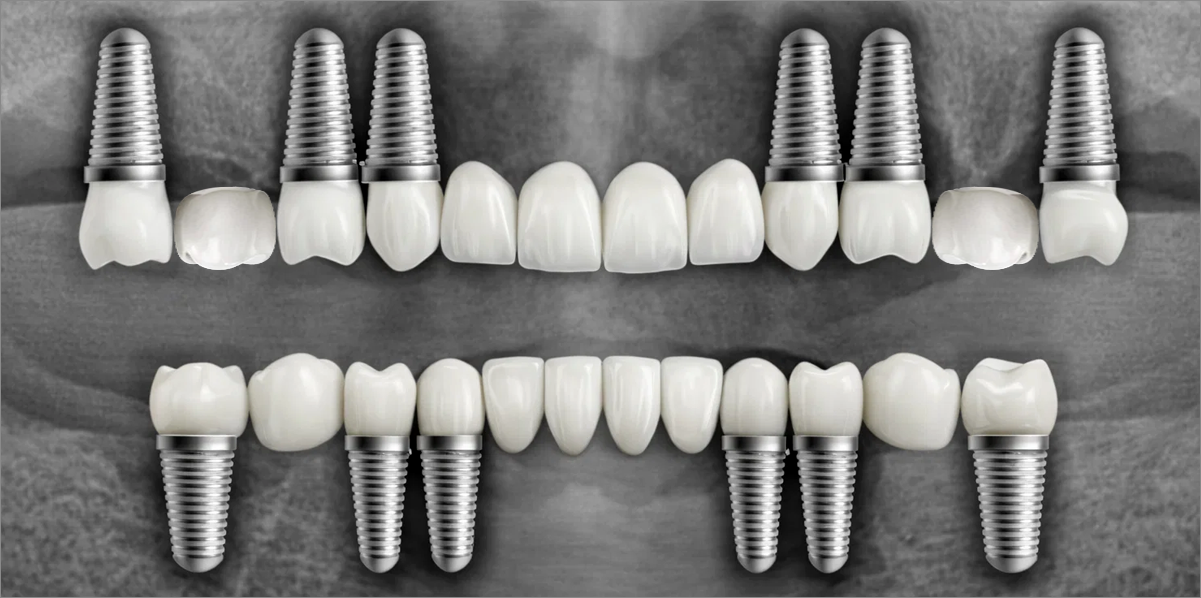

정확성 높은 식립의 노하우

3D 디지털 진단을 통한 체계적인 계획

전체 임플란트는 위턱과 아래턱의 교합, 잇몸뼈의 상태 및

얼굴 변화 등 모든 것을 고려해 식립해야 합니다.

서울더자연치과는 3D 디지털 기술의 정밀 진단을 바탕으로

수술 계획을 세워 수술을 집도합니다.

치료기간 : 2021.04.12~2021.09.15